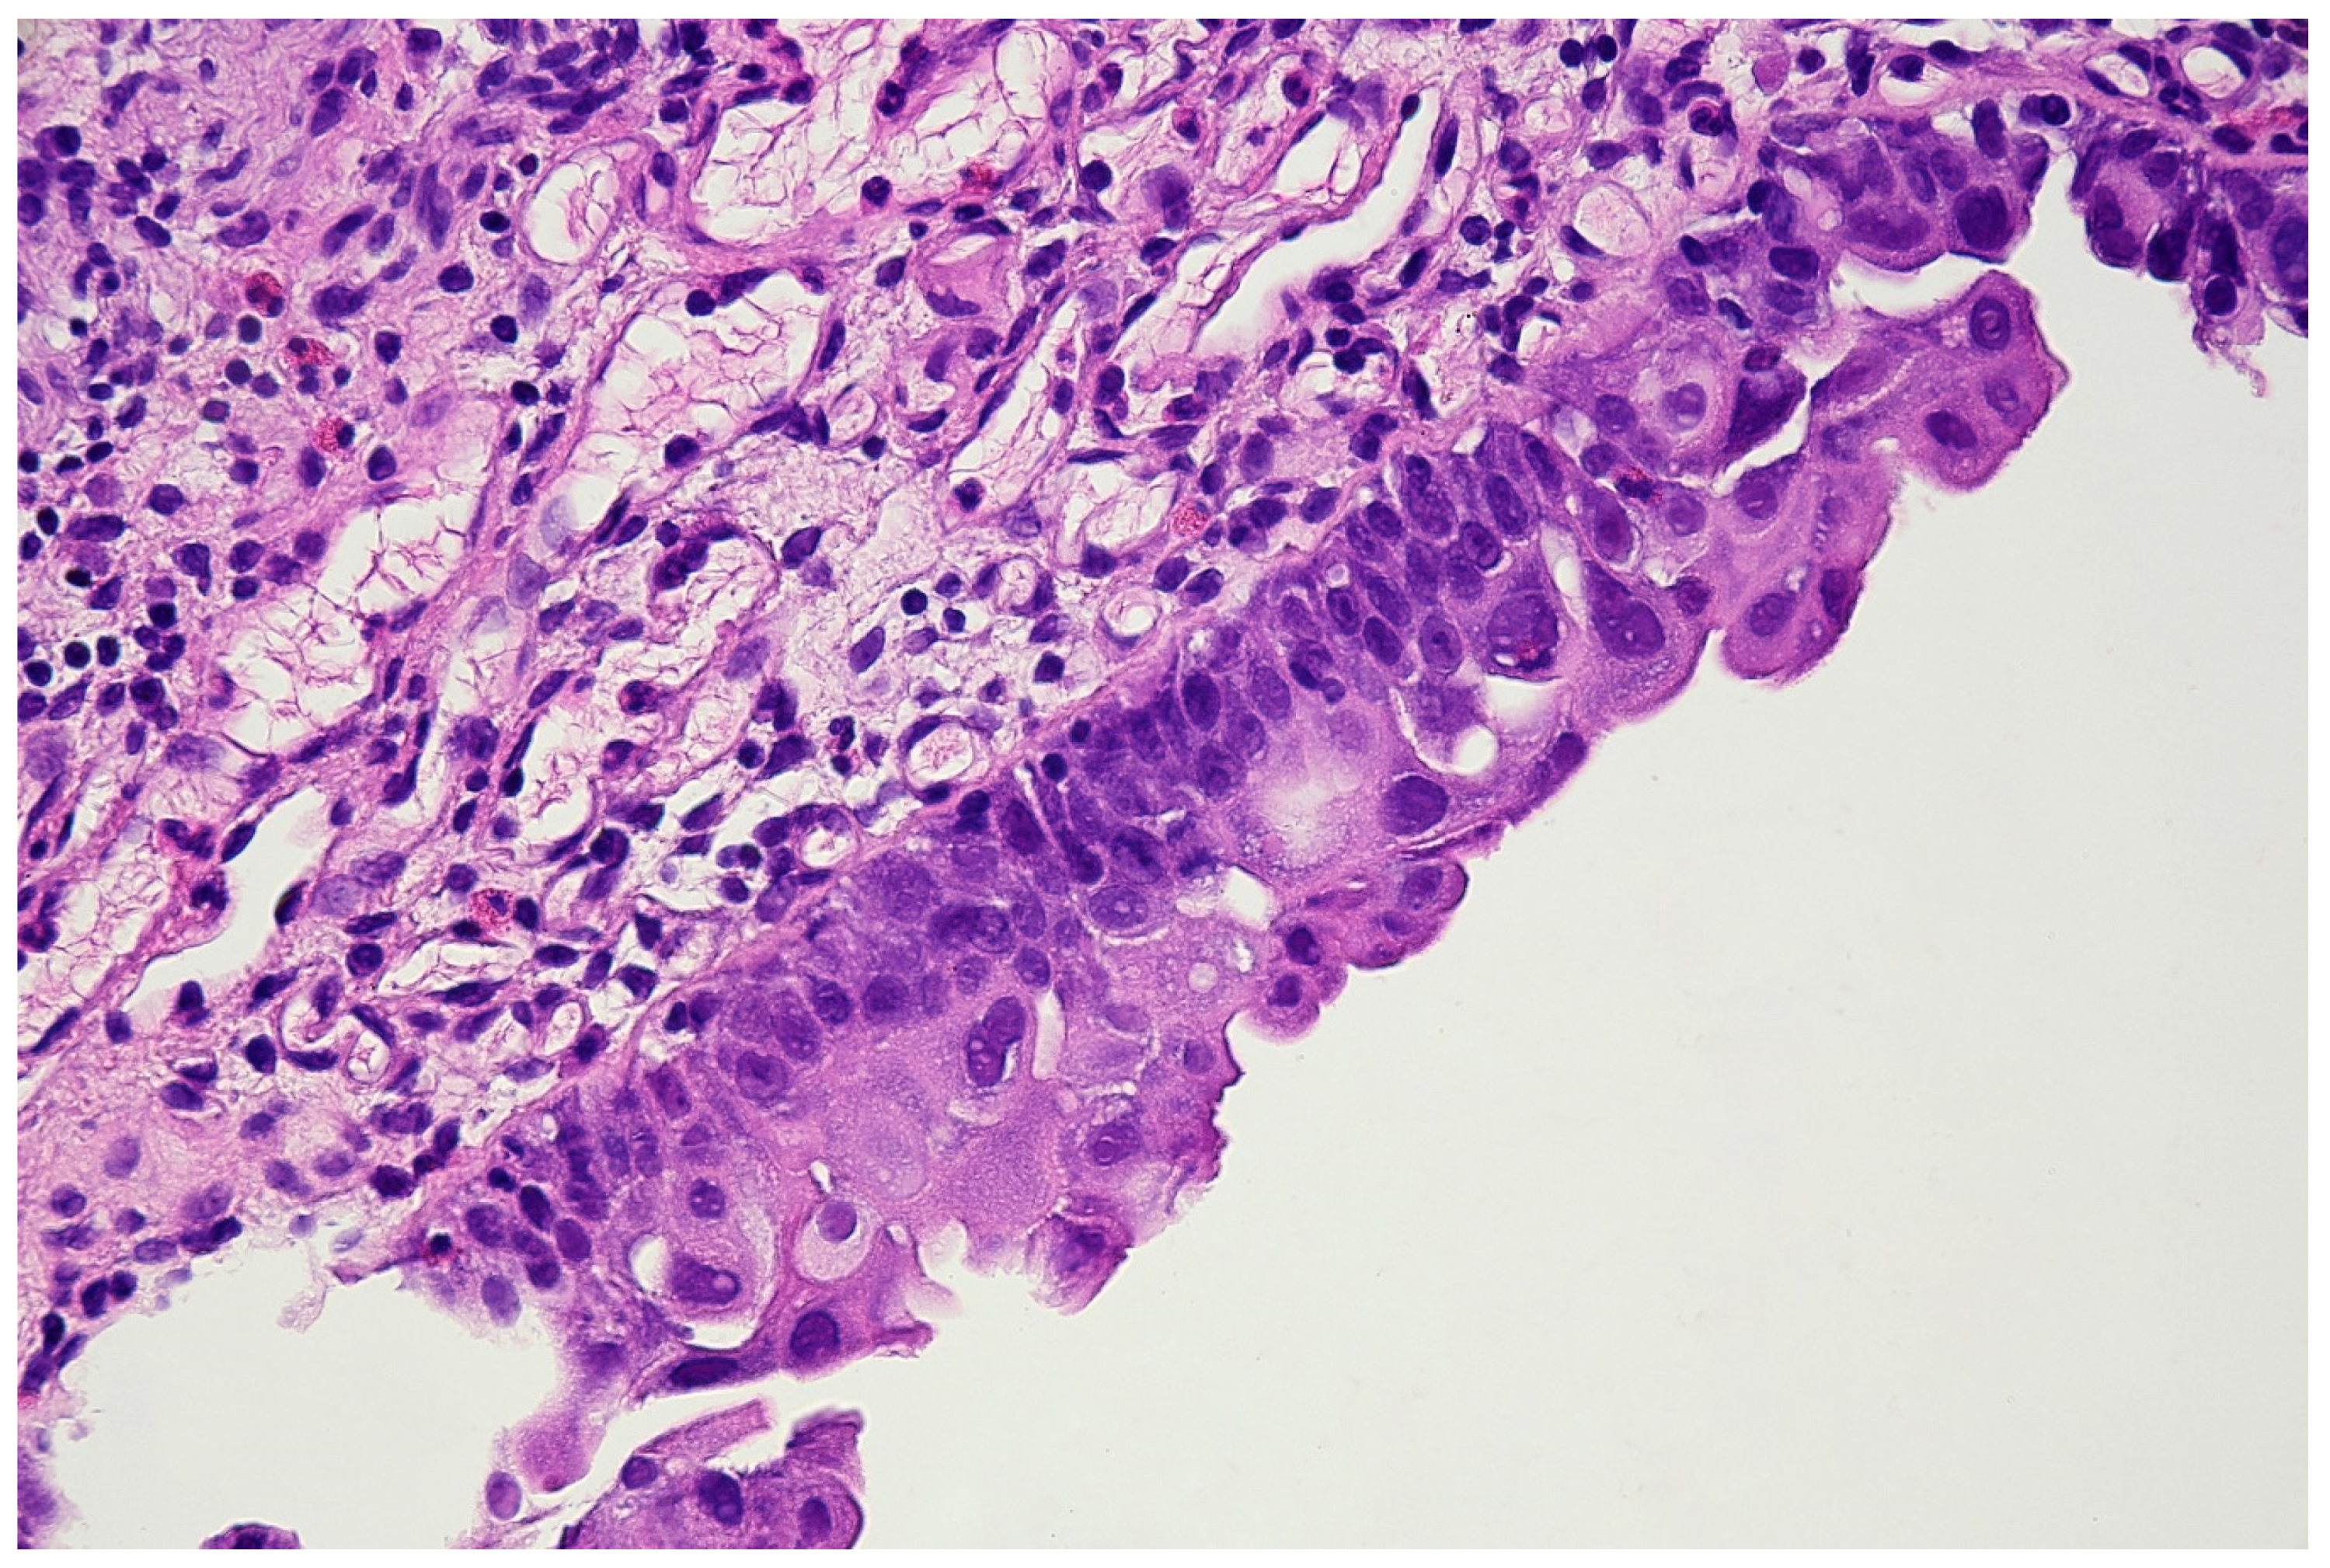

With the above-mentioned diagnostic data in hand, cystoscopy was carried out, undertaking a non-random bladder mucosa biopsy. Four specimens were collected, identifying urothelial carcinoma (HG CIS ICD-O code 8120/2) in each localisation and cystitis cystica, which could be responsible for the change seen in TRUS (see Figure 6 and Figure 7).

Figure 6.

Histopathological specimen—Haematoxylin and Eosin (H&E) staining. The bladder is covered with the epithelium, the cells of which show features of severe atypia. Atypical cells are visible in all the layers of the epithelium, including the external surface. Locally, a reduced number of cell layers can be seen. Nuclei are present with marked anisokaryosis, hyperchromasia, and sometimes, with irregularity of the nuclear membrane. The unbroken basement membrane is visible along the entire length of the epithelium; there is no invasion of atypical cells. Occasionally, mitoses with atypical division figures can be noted.